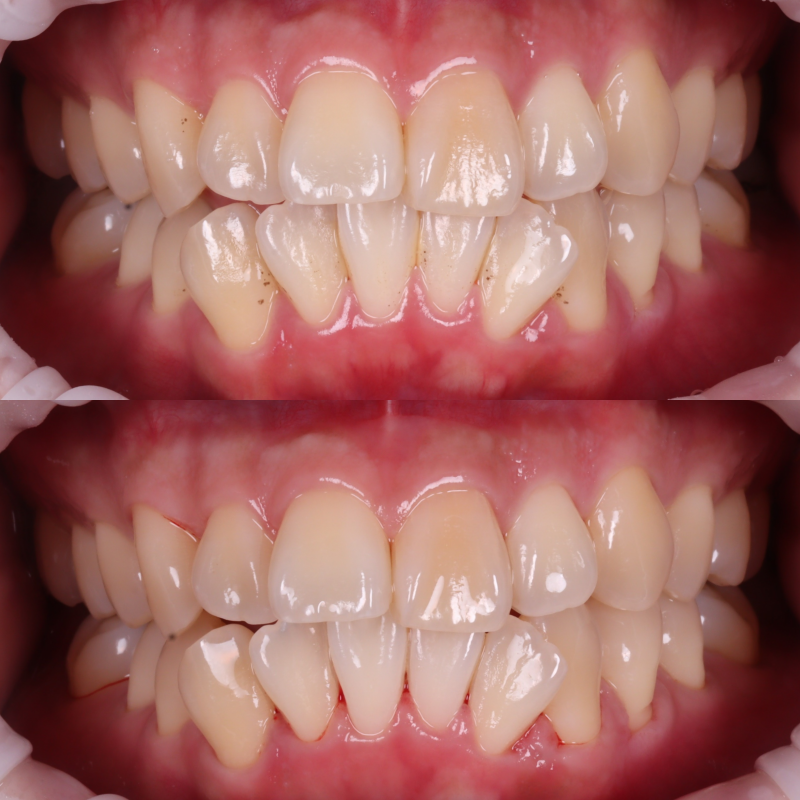

촬영일 : 250607

겉으로 보이는 표면에

착색이 도드라진 상태였고,

치아의 안쪽 면, 씹는 면 부근에

브라운 계열의 색소가 고착되어 있었습니다.

하지만 에어플로우로 착색을 제거하고 나니

치아 본연의 색이 드러났고

전체적으로 아주 깔끔해졌습니다.